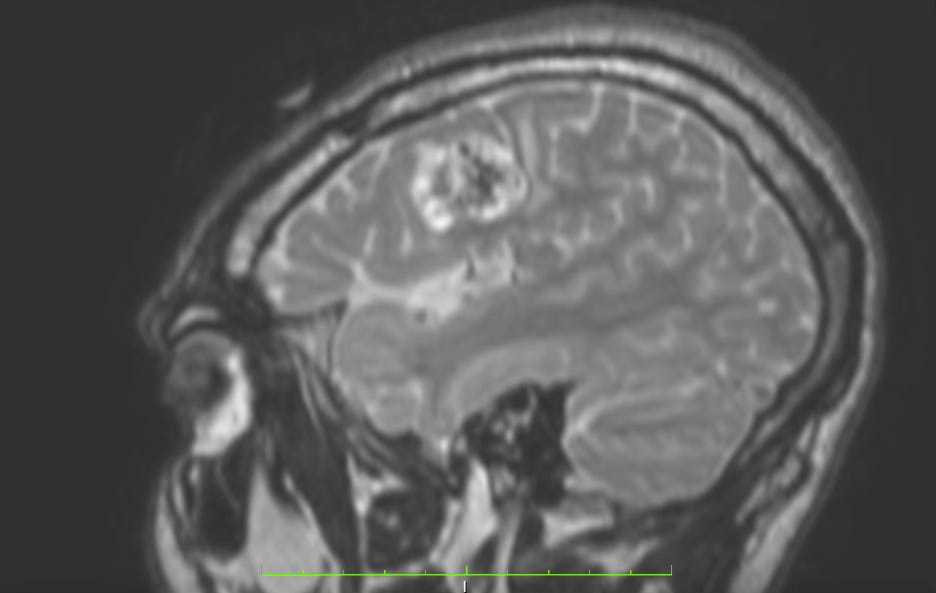

Let’s say you’ve just been diagnosed with a high grade glioma. You already have countless clinic letters that you can’t make sense of and you have had a bunch of scans you haven’t really seen, maybe briefly on a screen, but not properly, with all the different planes and looking carefully at each frame to distinguish what you are looking at with greater scrutiny and understanding.

What if you could gain access to all this information (it’s yours, so why not!) and make use of it to teach yourself more about your disease in simple, easy to understand terms, and then try to find solutions through the inquisitive type of brainstorming that, paired with ChatGPT, can provide powerful, insightful analysis which can provoke real thought about new options you may have not considered otherwise?

Sound good? Want to know more about what I mean? I’ll show you some examples of my thinking. This is anonymous data (because I don’t want to say who these individuals are for obvious reasons), but they provide useful examples of what I mean, in easy to follow steps.

Step 1: Information gathering